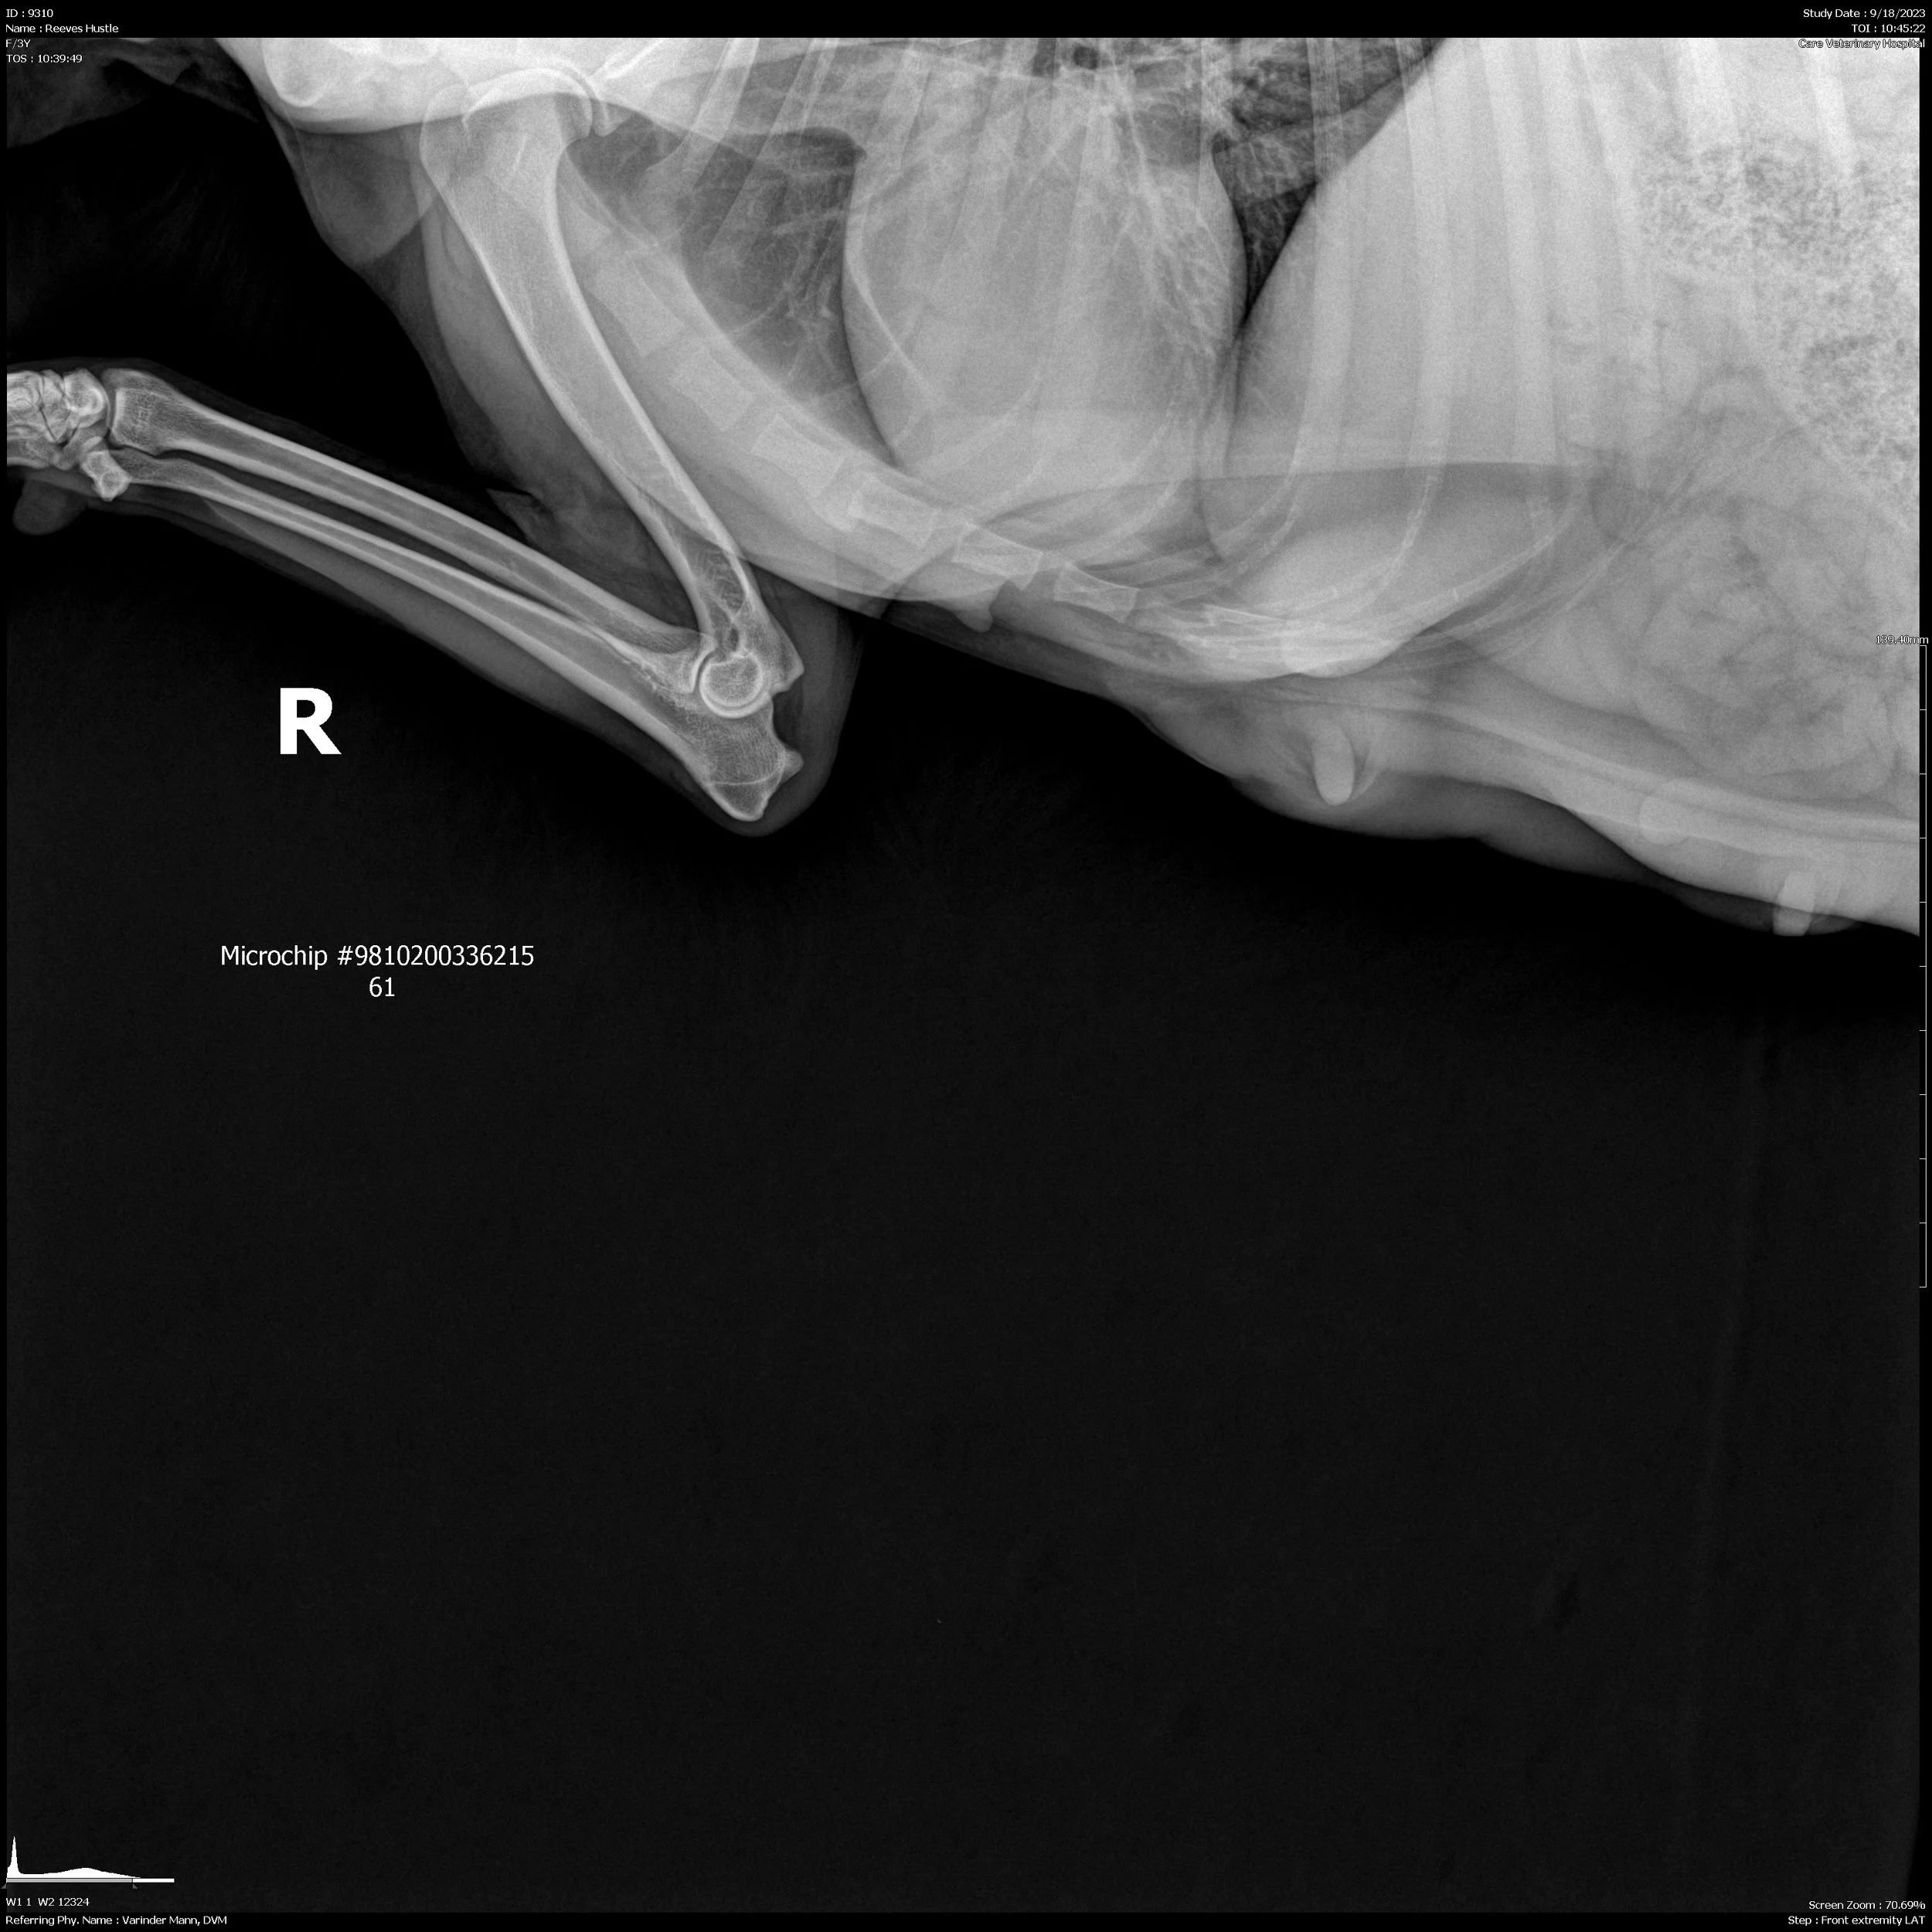

OFA Hips: Good

OFA Elbows: Normal